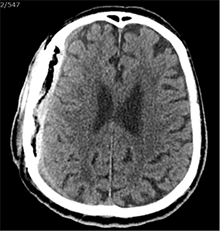

Praėjus dar 2 sav., pacientas iš slaugos ligoninės atvežtas dėl vangumo, dezorientacijos, nerišlios ir sulėtėjusios kalbos. Atlikus GKT, dešinėje pusėje po kraniotomijos lopu įtarta poūmė (ūmi) epidurinė hematoma, nesant VSD. Per parą pacientas operuotas. Operacijos metu po minkštaisiais audiniais rasta kraujo sankaupa su seroziniu komponentu, paimtas bakteriologinis pasėlis. Po KPL rasta krešulių su skystu krauju ir seroziniu komponentu. Paimtas antras bakteriologinis pasėlis, įtariant infekciją. Hematoma (seroma) pašalinta. Žaizda plauta mažos koncentracijos betadinu ir fiziologiniu tirpalu. Kraujavimo iš KSD nepastebėta. Nuspręsta KPL grąžinti – labiau tikėtina epidurinės seromos (EDS) diagnozė. Siekta uždaryti „negyvąjį“ epidurinį tarpą, pakabinant KSD centre prie KPL siūlais, tačiau KSD buvo nepaslankus, tampriai priaugęs prie smegenų. Atlikus kontrolinę GKT (9 pav.), nustatyta teigiamų pooperacinių pakitimų, smarkiai sustorėjęs KSD, tarpas tarp KPL ir KSD. VSD nenustatyta. Po operacijos paciento bendroji būklė buvo stabili. Reakcija buvo kiek sulėtėjusi, tačiau vyras gebėjo atsakyti į elementarius klausimus. Teigiama klinikinė dinamika. Po savaitės pacientas tapo labai vangus, sulėtėjo, skundėsi silpnumu, kalbėjo nesklandžiai. Pakartojus GKT (10 pav.), nustatyta padidėjusi epidurinė skysčio sankaupa, panaši į mišraus tankio hematomą (apie 64 ml tūrio) dešinėje pusėje frontotemporoparietaliai, padidėjusi VSD į kairę – iki 4 mm. Kadangi pacientas per tą patį randą jau operuotas 6 kartus, o po operacijų pastebimos vis atsinaujinančios pakartotinės EDS, priimtas sprendimas neskirti operacinio gydymo. KPL turėjo daugybinių perforacijų, todėl nuspręsta atlikti subgalinio tarpo punkciją, tikintis, kad per perforacijas išbėgs EDS. Atlikus punkciją, gauta 20 ml serohemoraginio skysčio. Po procedūros paciento būklė pagerėjo, jis tapo kiek aktyvesnis, tačiau efektas nebuvo patenkinamas. Kitą dieną nuspręsta punktuoti pakartotinai, gauta 4 ml serohemoraginio skysčio. Tūris buvo nepakankamas teigiamam efektui gauti. Priimtas sprendimas skirti lašinių infuzijų ir švelnią osmoterapiją neurologinei simptomatikai sumažinti. Punkcijos nedavė norimo efekto, todėl nuspręsta suformuoti poodinę neigiamo slėgio drenažinę sistemą po minkštųjų audinių lopu. Į subgalinį tarpą įvestas 20G periferinės venos kateteris, fiksuotas prie odos ir sujungtas su uždara vakuumine sistema, tikintis nuolatinio drenavimosi smegenų kompresijai sumažinti. Per 5 lovadienius išsiskyrė apie 50 ml serohemoraginio skysčio. Atlikus kontrolinę GKT, buvo matyti teigiama dinamika (11 pav.). Dėl infekcijos profilaktikos vakuuminė sistema pakeista 2 kartus. Įvedus vakuuminę sistemą, po 12 lovadienių paciento būklė pagerėjo, jis tapo aktyvesnis, į klausimus atsakydavo prasmingai, paliepimus vykdydavo visomis galūnėmis. Vakuuminė sistema pašalinta. Po 2 dienų atlikta GKT (12 pav.). EDS dešinėje pusėje regresavo, smegenų kompresijos nenustatyta. Esant stabiliai būklei ir teigiamai dinamikai, pacientas grąžintas į slaugos ligoninę.

10 pav. Bėgant laikui, padidėjusi EDS (dešinėje F-T-P, padidėjusi VSD į kairę iki 4 mm)